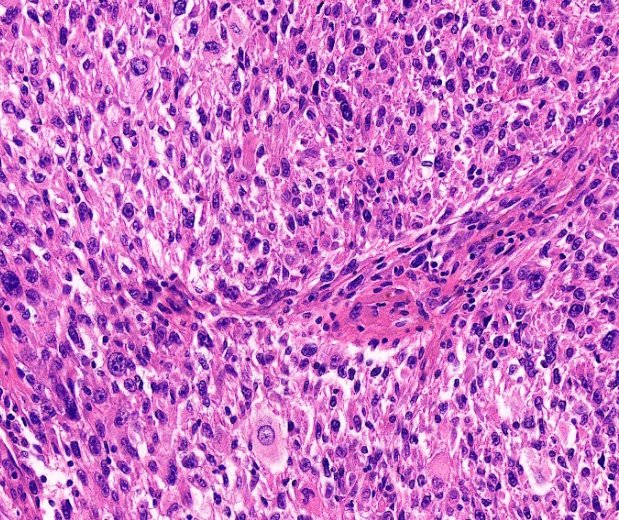

入驻企业展示【第一期】“智能化病理诊断解决方案供应商”英特美迪!时间:2022-05-18 广州英特美迪科技有限公司 英特美迪科技有限公司是一家专注于数字病理应用系统和人工智能辅助诊断系统研发生产的高科技医疗信息技术企业。公司创立于2018年,创始人团队拥有海外知名学府留学背景,拥有独立的AI算法和硬件研发团队,利用在精密光学、人工智能、云计算等领域领先的技术优势,以及拥有海量医学专家标注的病理影像数据库,打造高度自动化的AI辅助诊断应用平台和病理影像扫描与存储系统,以推动临床病理医学的数字化、智能化发展为公司的使命。 目前,英特美迪科技有限公司已通过中关村金种子企业认证、2021年获得“鹭创未来”海外创业大赛暨第五届中国厦门海外(美国)创业大赛“一等奖”、2021年入选第四届粤港澳大湾区生物科技创新企业50强“新锐企业”并连续两年获得中国双创大赛“优胜企业”奖等荣誉。 ![]() ![]() ![]() ![]() 图 | 企业部分荣誉 行业背景 病理是癌症诊断的金标准,癌症的临床病理评估对病人的治疗和预后起着决定性的作用 行业痛点 + 1)人才稀少:根据卫生部〔2009〕31号《病理科建设与管理指南(试行)》全国医院应配病理医生:10万名,目前在册病理医生:仅1万人; 2)资源不均:病理医生主要集中大型综合型医院,基层医疗机构人员配置紧缺、业务能力较低; 3)效率低下: 数字化发展进程较慢,传统显微镜下工作模式效率低、强度大,误差率高,标准难统一。 解决方案 自主研发产品 IMD-Neo-5X介绍 英特美迪 ➡ IMD-Neo-5X自动设备 ![]() • 玻片扫描影像系统 • 全自动封片染色一体机 • 全自动免疫组化染色机 ➡ IMD-Neo-5X智能辅诊系统 ![]() • 宫颈癌筛查系统 • 免疫组化定量分析系统 • 组织病理智能诊断系统 ➡ IMD-Neo-5X病理信息化系统 ![]() • 病理科信息系统 • 数字切片PACS系统 • 远程会诊系统 ▌ IMD-Neo-5X-配置参数 由英特美迪自主研发的IMD-Neo-5X病理切片扫描影像系统目前已经获得了国家药品监督管理局注册批件,注册证编号:粤械注准20202221444。其采用高速面阵CMOS光学扫描元件,将病理玻片实体使用高清晰的成像系统捕捉为全切片数字图像,输出的数字图像具备高分辨率、无缝隙、真实还原目视镜下色彩、高速缩放等特征。配置参数如下: ★ 加载数量:全自动一键式扫描,无人值守,单次加载1-5张切片,根据需要可在不更换主机的前提下拓展最大装载切片150片 ★ 扫描倍率:20X或40X高速扫描 ★ 高品质物镜:双物镜;20X 、40X Plan APO无限远平场复消色差物镜;20X 镜头孔径≥0.75NA,40X镜头数值孔径≥0.95NA ★ 扫描分辨率:20X,分辨率≤0.28μm/像素;40X,分辨率≤0.15μm/像素扫描速度:扫描15mmX15mm面积的组织,在20X情况下,扫描时间≤120s,40X:扫描时间≤240s 技术特点 英特美迪 1、高性能扫描 A、高质量浏览体验; B、无人值守扫描; C、多层景深融合; D、自动条码识别 ; ![]() 3、智能算法 A、宫颈细胞学辅助筛查 B、结核杆菌自动识别 C、Ki67定量分析 ![]() ![]() 2、深度软件整合 A、流程优化 B、病例管理 C、远程会诊 ![]() ![]() 应用场景 英特美迪 1 病理科切片存储形式